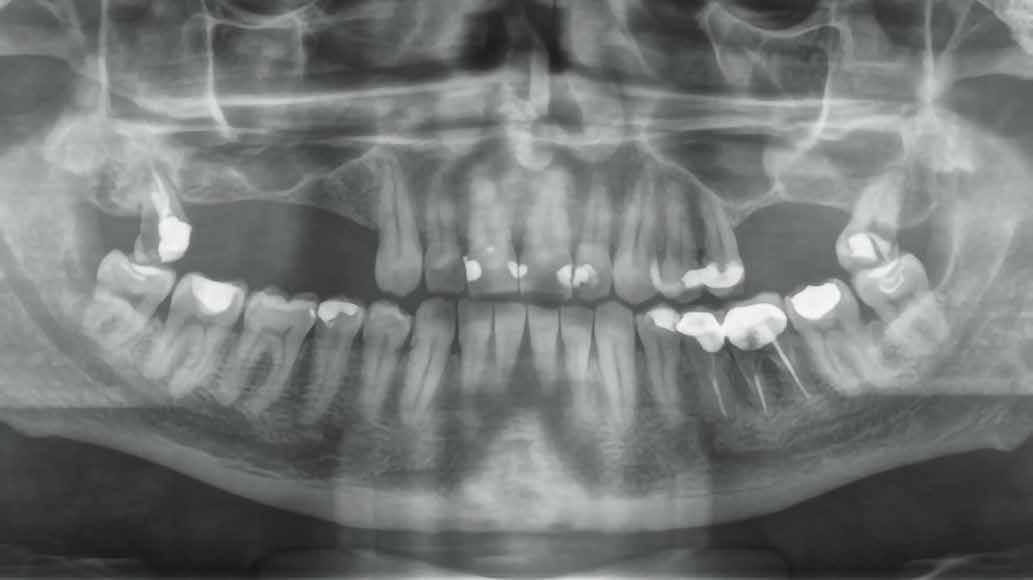

A 68 éves nőpáciens, panaszt (fájdalom, ráharapási érzékenység) okozó bal oldali felső, első kisőrlő foga miatt jelentkezett rendelőnkben. Az általános anamnézisben említést érdemlő betegség, műtét nem szerepel. Az elvégzett klinikai és radiológiai vizsgálatok (1., 2. ábra) endo-parodontális érintettséget igazoltak, vertikális fraktúra gyanújával. A fog harmadfokban mozgatható volt, a bukkális oldalon 14 mm-es tapadásveszteséggel. A reménytelen parodontális prognózis a fog eltávolításának abszolút indikációját jelentette. Hídpótlás készítéséhez a szemfog előkészítése lett volna szükséges, illetve csak vegyesen rögzített (implantátum-fog) hídpótlás készítése lett volna lehetséges. Figyelembe véve a szemfog anyagának védelmét, parodontális állapotát (a szemfognál is észlelhető volt tapadásveszteség, noha a fog stabil volt) és azt a tényt, hogy a szakirodalomban nem találtunk egyértelmű ajánlást vagy vizsgálatot, amely megbízhatóan alátámasztaná az ilyen státuszban fogon és implantátumon vegyesen rögzített protetikai megoldás hosszú távú megfelelőségét, a preoperatív konzultáció során, a pácienssel egyeztetve a hídpótlás készítését elvetettük, és implantációs fogpótlás készítése mellett döntöttünk. A protetikai szemléletű,

„visszafelé” tervezés elveit követtük a hosszú távú funkcionális, esztétikai siker és szöveti stabilitás elérése érdekében. Ezek alappillére az implantátum megfelelő pozicionálása, amelyre akkor nyílik lehetőségünk, ha a fog eltávolítását követően megfelelő mennyiségű és minőségű csontkínálattal rendelkezünk. A páciens kivizsgálása és megfelelő előkészítése után, a fog eltávolításával egy időben PRF Stikcy Bone™ segítségével kivitelezett alveólus prezerváció mellett döntöttünk, a megfelelő mennyiségű és minőségű csontos és mukogingivális gyógyulás elősegítése érdekében. A PRF készítmény mennyiségét, minőségét, kezelhetőségét és hatékonyságát jelentősen befolyásolják a páciens laborértékei, ezért a PRF csont augmentáció esetén, a műtétet megelőzően mindig laborvizsgálatot végzünk (hemoglobin: 134 g/liter, hematokrit: 0,43, fehérvérsejt: 6,6 G/ liter, CRP: 3,60 mg/liter, vércukor: 5,2 mmol/liter, összkoleszterin: 7,00 mmol/liter, triglicerid: 1,28 mmol/liter, HDL koleszterin: 1,02 mmol/liter, LDL koleszterin: 4,8 mmol/ liter), D3-vitamin: 117,5 nmol/liter).

1. ábra: Megfelelő szájhigiénia – panorámaröntgen. 2. ábra: A 2.5, 2.6 és 2.7-nek megfelelő terület a röntgenfelvételen.

és jelentős mobilitással rendelkezett. A radiológiai vizsgálat után egyértelműen látszódott, hogy a fogon még nem végeztek gyökérkezelést. A 2.6-os és 2.7-es fogaknak megfelelő területen az arcüreg kiterjedése jelentős volt, vertikális csontmennyiség szignifikánsan csökkent (1. és 2. ábra).